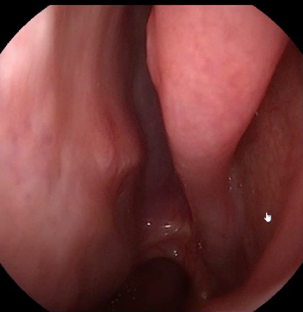

Q

Fall 2

• 70-årig kvinna med nästäppa, nedsatt luktsinne och förvärrad astma

Vad ser vi i näsan?

Behandling?

A

• Polyper (grad 3)

• Behandling: nasal steroid, skölja med koksalt, nedtrappningskur med peroral kortison också.